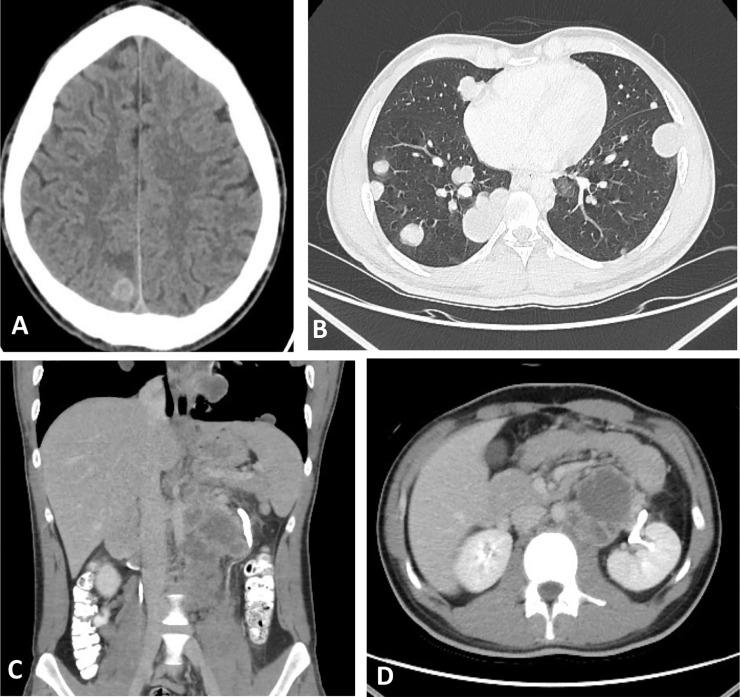

Pure testicular choriocarcinoma is an extremely rare subtype of nonseminomatous germ cell tumor, accounting for less than 1% of all germ cell tumors and only 0.19% of all testicular tumors. It is a highly aggressive malignant tumor with early multiorgan metastasis and poor prognosis. We present a case of 23-year-old male presented to the hospital with mild hemoptysis which was thought as a sequela of his past COVID-19 pneumonia infection, however; chest radiograph showed multiple rounded cannonball opacities seen throughout both lungs raising the suspicion of metastatic deposits to the lungs. During physical examination, left testicular painless swelling was noted leading to an ultrasound of the scrotum which revealed a left intratesticular infiltrative, heterogeneous mass. Tumor markers, including beta-human chorionic gonadotropin, lactate dehydrogenase and alpha fetoprotein were extremely high. Computed tomography scan of the brain, chest, abdomen, and pelvis showed hemorrhagic metastatic deposits to the brain, chest, and left para-aortic lymph nodes. The patient underwent radical orchiectomy and histopathology reports confirmed the diagnosis of pure testicular choriocarcinoma.

纯睾丸绒毛膜癌是一种极其罕见的非精原细胞瘤性生殖细胞肿瘤亚型,占所有生殖细胞肿瘤的比例不到1%,仅占所有睾丸肿瘤的0.19%。它是一种侵袭性很强的恶性肿瘤,早期多器官转移且预后较差。我们报告一例23岁男性患者,因轻度咯血入院,最初认为是既往新冠病毒肺炎感染的后遗症;然而,胸部X线片显示双肺多发圆形炮弹样阴影,怀疑有肺部转移灶。体格检查时,发现左侧睾丸无痛性肿大,遂行阴囊超声检查,结果显示左侧睾丸内有浸润性、不均匀肿块。包括β-人绒毛膜促性腺激素、乳酸脱氢酶和甲胎蛋白在内的肿瘤标志物极高。脑部、胸部、腹部和骨盆的计算机断层扫描显示脑部、胸部和左主动脉旁淋巴结有出血性转移灶。患者接受了根治性睾丸切除术,组织病理学报告确诊为纯睾丸绒毛膜癌。